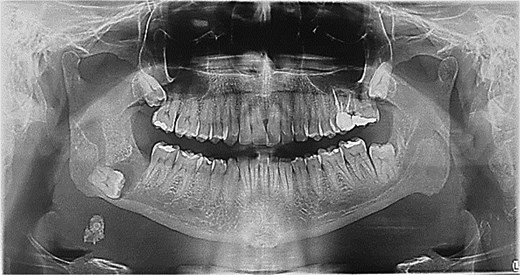

A 49-year-old male patient was referred, after a radiographic finding in a panoramic radiography, for evaluation of the lower right third molar (48) in an ectopic position associated with a radiolucent image, which suggested a cystic lesion (Fig. 1). A cone-beam computed tomography was made. The 3D imaging exams showed the presence of tooth 48 in the mandibular base, in the right angle region, associated with the radiolucent image, lingual fenestration, and intimate relationship between the third molar and the mandibular canal (Fig. 2). Due to the dental position, to have better visualization and less morbidity a submandibular extraoral approach was planned. The tooth removal and cyst curettage were made through the Risdon approach (Fig. 3). A fixation system with reconstruction plate (2.4 mm) was used to prevent a mandibular pathological fracture (Fig. 4). Anatomopathological examination of the cystic capsule was performed with a diagnosis of dentigerous cyst. In the postoperative period, the patient reported alteration in the sensitivity of the inferior alveolar nerve. Postoperative radiographic examinations showed adequate adaptation of the fixation system and complete surgical removal of the tooth and associated lesion. Orthopantomography with 4 months follow-up showed bone repair and adequate adaptation of the fixation system (Fig. 5).